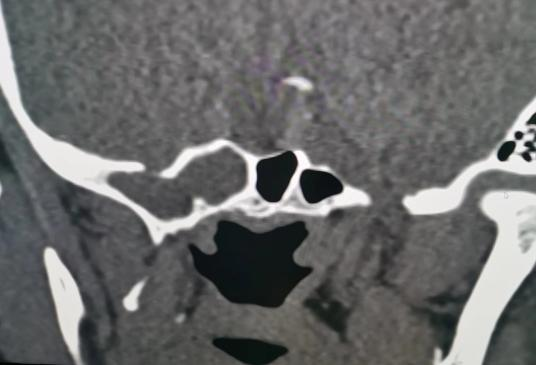

耳鼻咽喉头颈外科副主任医师宋建涛及主治医师王向锋、CT室主任刘康为患者进行详细影像学检查,确定脑脊液鼻漏的准确位置,同时积极完善鼻内镜等相关术前常规检查。6月3日为两位患者成功实施鼻内镜下脑膜脑膨出切除、脑脊液鼻漏阔筋膜修补术。经过精心护理,患者恢复良好,现均已出院。